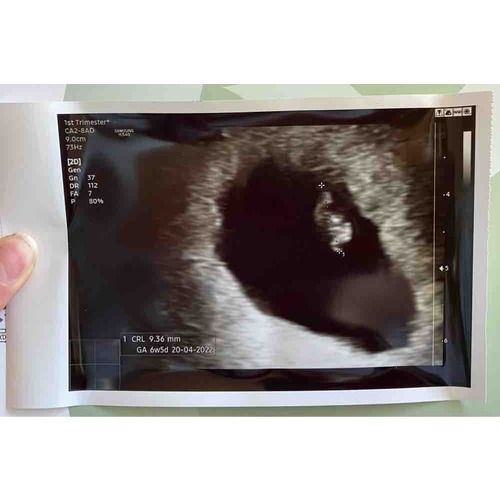

Ook ik heb vandaag de eerste echo gehad! Ik dacht bijna 8 weken te zijn, maar toch teruggezet naar 6w5d! Wel een heel mooi kloppend hartje gezien en metingen waren goed